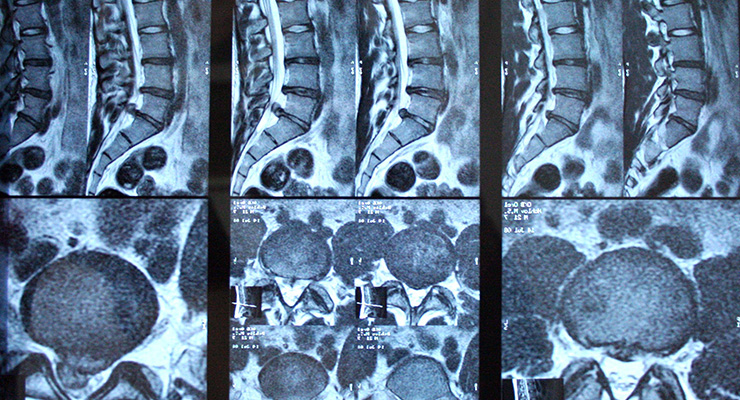

Диагностика спондилеза

Для постановки точного диагноза заболевания позвоночника необходимо провести комплексное лечение с помощью специального медицинского оборудования. Наиболее информативный способ обследования , МРТ и компьютерная томография. Врач может назначить оба обследования или выбрать один из методов. Они позволяют выявить поврежденный участок позвоночника, определить расположение и размеры отростков. Рентгенография позвоночника дает информацию о локализации, обширности и стадии поражения.

Важным диагностическим этапом является определение площади патологии и характера костных образований. При спондилезе затронуто 1-3 позвонка, выражено окостенение, наросты имеют неправильную форму, могут быть направлены вверх, вниз, срастаться по принципу «,клюва попугая», и даже окольцовывать позвонок.

При остеохондрозе наросты расположены перпендикулярно позвоночнику, нет тенденции к сращиванию. Болезнь Форестье затрагивает больший участок с деформацией более 3 позвонков.